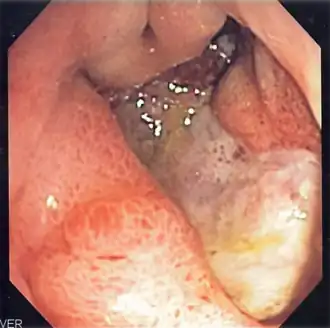

Úlcera péptica é uma lesão no revestimento do estômago, no duodeno ou, raramente, na parte final do esófago.[1][7] Uma úlcera no estômago denomina-se úlcera gástrica, enquanto que uma no duodeno se denomina úlcera duodenal. Os sintomas mais comuns são acordar de noite com dor na parte superior do abdómen ou dor na parte superior do abdómen que melhora ao comer. A dor é muitas vezes descrita como ardor ou dor ligeira constante. Entre outros possíveis sintomas estão a eructação, vómitos, perda de peso ou perda de apetite. Cerca de um terço das pessoas não manifesta sintomas.[1] Entre as possíveis complicações estão a hemorragia gastrointestinal, perfuração gastrointestinal e obstrução da saída gástrica. Cerca de 15% das pessoas apresentam hemorragia.[2]

As causas mais comuns são a bactéria Helicobacter pylori e os anti-inflamatórios não esteroides.[1] Entre as outras possíveis causas está o fumar, o stresse devido a doença grave, a doença de Behçet, a síndrome de Zollinger-Ellison, a doença de Crohn e a cirrose hepática.[1][3] As pessoas idosas são mais sensíveis aos efeitos dos anti-inflamatórios não esteroides. O diagnóstico pode ser suspeitado com base nos sintomas e confirmado com endoscopia ou ingestão de bário. A presença de H. pylori pode ser confirmada com análises ao sangue que detectam a presença de anticorpos, com um teste rápido da urease, com exames às fezes para observar sinais da bactéria ou com uma biópsia do estômago. Entre outras doenças que produzem sintomas semelhantes à úlcera péptica estão o cancro do estômago, a doença arterial coronária, a inflamação do revestimento do estômago ou cálculos na vesícula.[1]